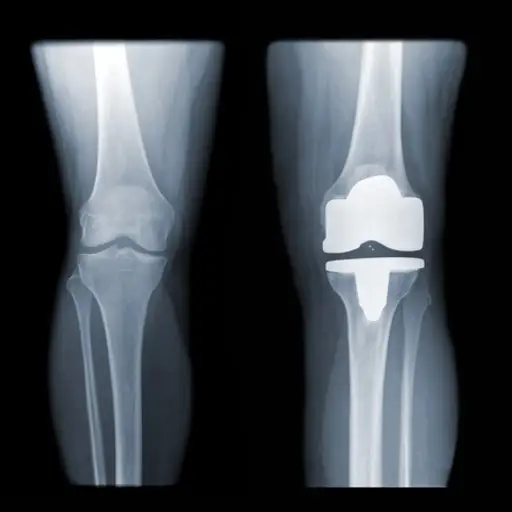

骨关节炎

当关节周围的软骨恶化时,就会引起一种叫做退行性关节疾病骨关节炎.肥胖迫使关节承担大量的重量,从而导致磨损。这是一种非常痛苦的疾病,会降低灵活性,并伴有僵硬和疼痛。